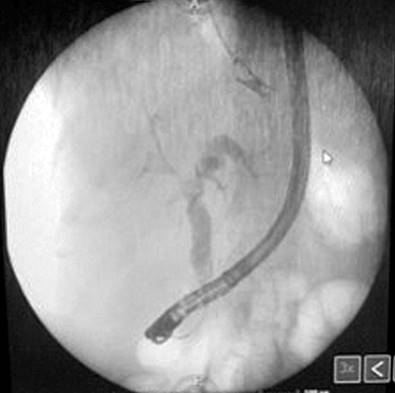

On her last visit, the patient went to the emergency room with the symptoms described above, leukocytosis, increased bilirubin, cholestasis enzymes (Table 1), and jaundice in the sclera and mucous membranes. The diagnosis of cholangitis was assessed, for which an MRE cholangiography was performed, showing new findings in favor of multiple intrahepatic cystic lesions with an annular enhancement of the contrast medium and dilation of the intrahepatic and extrahepatic bile ducts. These findings were consistent with Caroli’s disease. An intervention with endoscopic retrograde cholangiopancreatography (ERCP) was made, in which a sphincterotomy was performed before cannulation. The discharge of choledocholithiasis and seropurulent content consistent with cholangitis was observed, later placing a 10 Fr/9 cm plastic prosthesis (Figure 3).